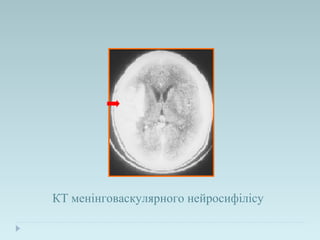

КТ менінговаскулярного нейросифілісу